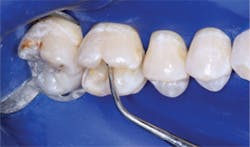

- Place resin-modified glass ionomer on the deepest areas of the tooth preparation, not on the margins. The material should be about 0.5 mm thick or slightly thicker. Cure it.

- Place the self-etch bonding agent of your choice. The bonding brands noted in this article have well-proven excellent results on dentin and enamel without total etching. Although when total-etch is done well it is successful, our research shows it creates significantly more unpredictable postoperative tooth sensitivity than self-etch techniques.

- Place the restorative resin in increments, starting with 0.5 mm in the deepest portion of the box form, increasing to 1.0 mm and finally to 2.0 mm increments. Clinicians Report research has shown that currently popular curing lights do not cure the entire depth of a typical box form at 7 mm.